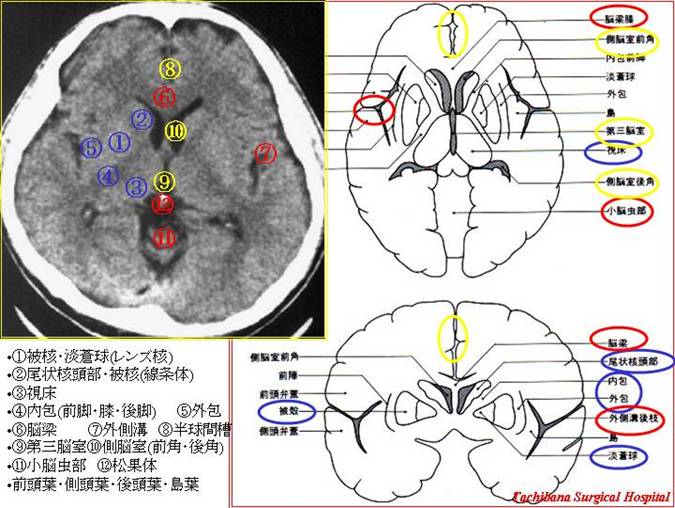

画像診断 脳血管名古屋~春日井の脳神経外科勝川脳神経クリニック。

頭部CT – 循環器内科.com。